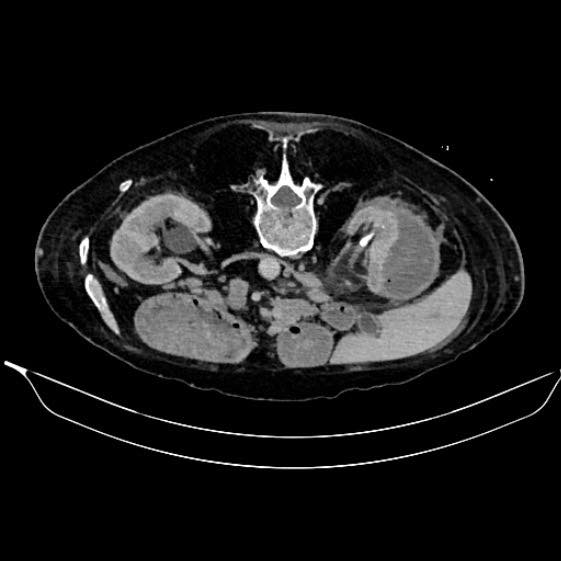

Όπως ανακοίνωσε η διοικήτρια του νοσοκομείου, πραγματοποιήθηκε παροχέτευση περινεφρικού αποστήματος υπό αξονική καθοδήγηση, σε έναν ιδιαίτερα απαιτητικό και σηπτικό ασθενή που βρισκόταν υπό αντιπηκτική αγωγή.